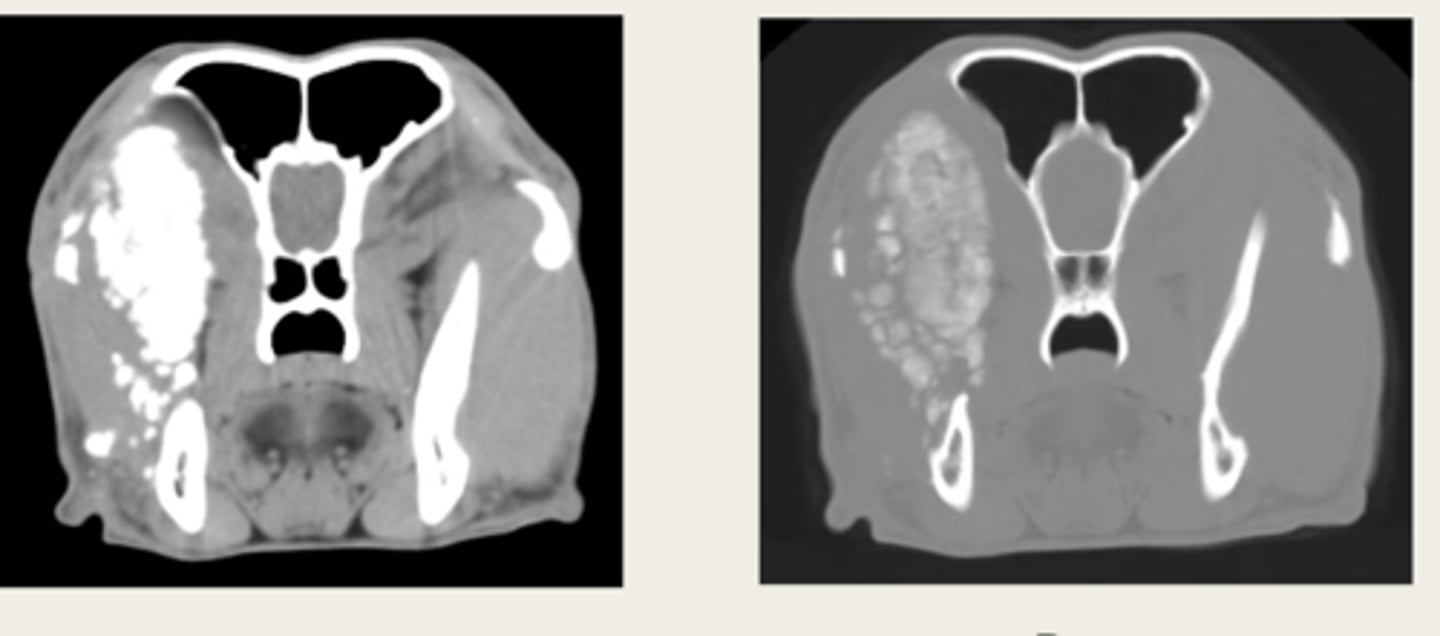

left- bone window

right- tissue window

which CT window shows bone window or tissue window?

left- soft tissue window

right- bone window

ID the CT windows

left- pre contrast

right- post contrast

window- soft tissue window

which CT images are pre and post contrast? what type of window is being shown in both?